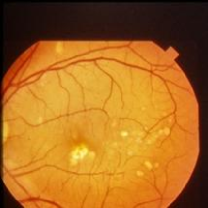

4.3 Style Transferring Neural Networks

Style transferring neural network in [16] was modified to generate new disease images. This network adopts layers from ”conv1 1” to ”conv4 1” in pre-trained VGG-19 [24] network for the encoder, whose weights are provided by ImageNet-pretrained weights. What’s more, multi-level stylization strategy proposed in [16] is applied to optimize the VGG features in different layers. Input images are three CFP images and three FA images as style images shown in Fig. 2 and 5. Six CFP images with three drusen and three GA images in Fig. 3 and Fig. 4. Also, FA images are applied to generate new images in Fig. 6 and Fig. 7. For CFP images, six images are shown in Fig. 3 and in Fig. 4. In Fig. 3, generated images contain round, discrete yellow-white dots, which are the symptom of drusen. In the same way, in Fig. 4, well-demarcated areas appear on the three images. Therefore, style transferring can generate new retinal symptom images.

Figure 3: Three CFP fundus images with symptom of drusen and corresponding generated images. (a), (b), (c) Original images. (d), (e), (f) Generated images.